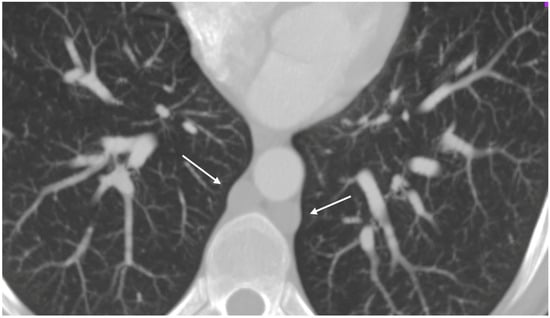

A respiratory alkalosis was found at the blood gas analysis so in suspicion of PE, Computed Tomography Angiography (CTA) was performed and did not detect any sign of pulmonary thromboembolism but azygos and hemiazygos vein dilatation (Figure 1) and a congenital abnormality of the IVC, in addition to DVT of iliaco-femoral veins with involvement of the IVC, renal veins, and mesenteric vein (Figure 2). Anticoagulation with low molecular weight heparin (LMWH) 1 mg/kg every 12 h subcutaneously was started.

Figure 1.

Thoracic angio-TC: dilated azygos and hemiazygos veins (arrows); no pulmonary embolism signs.